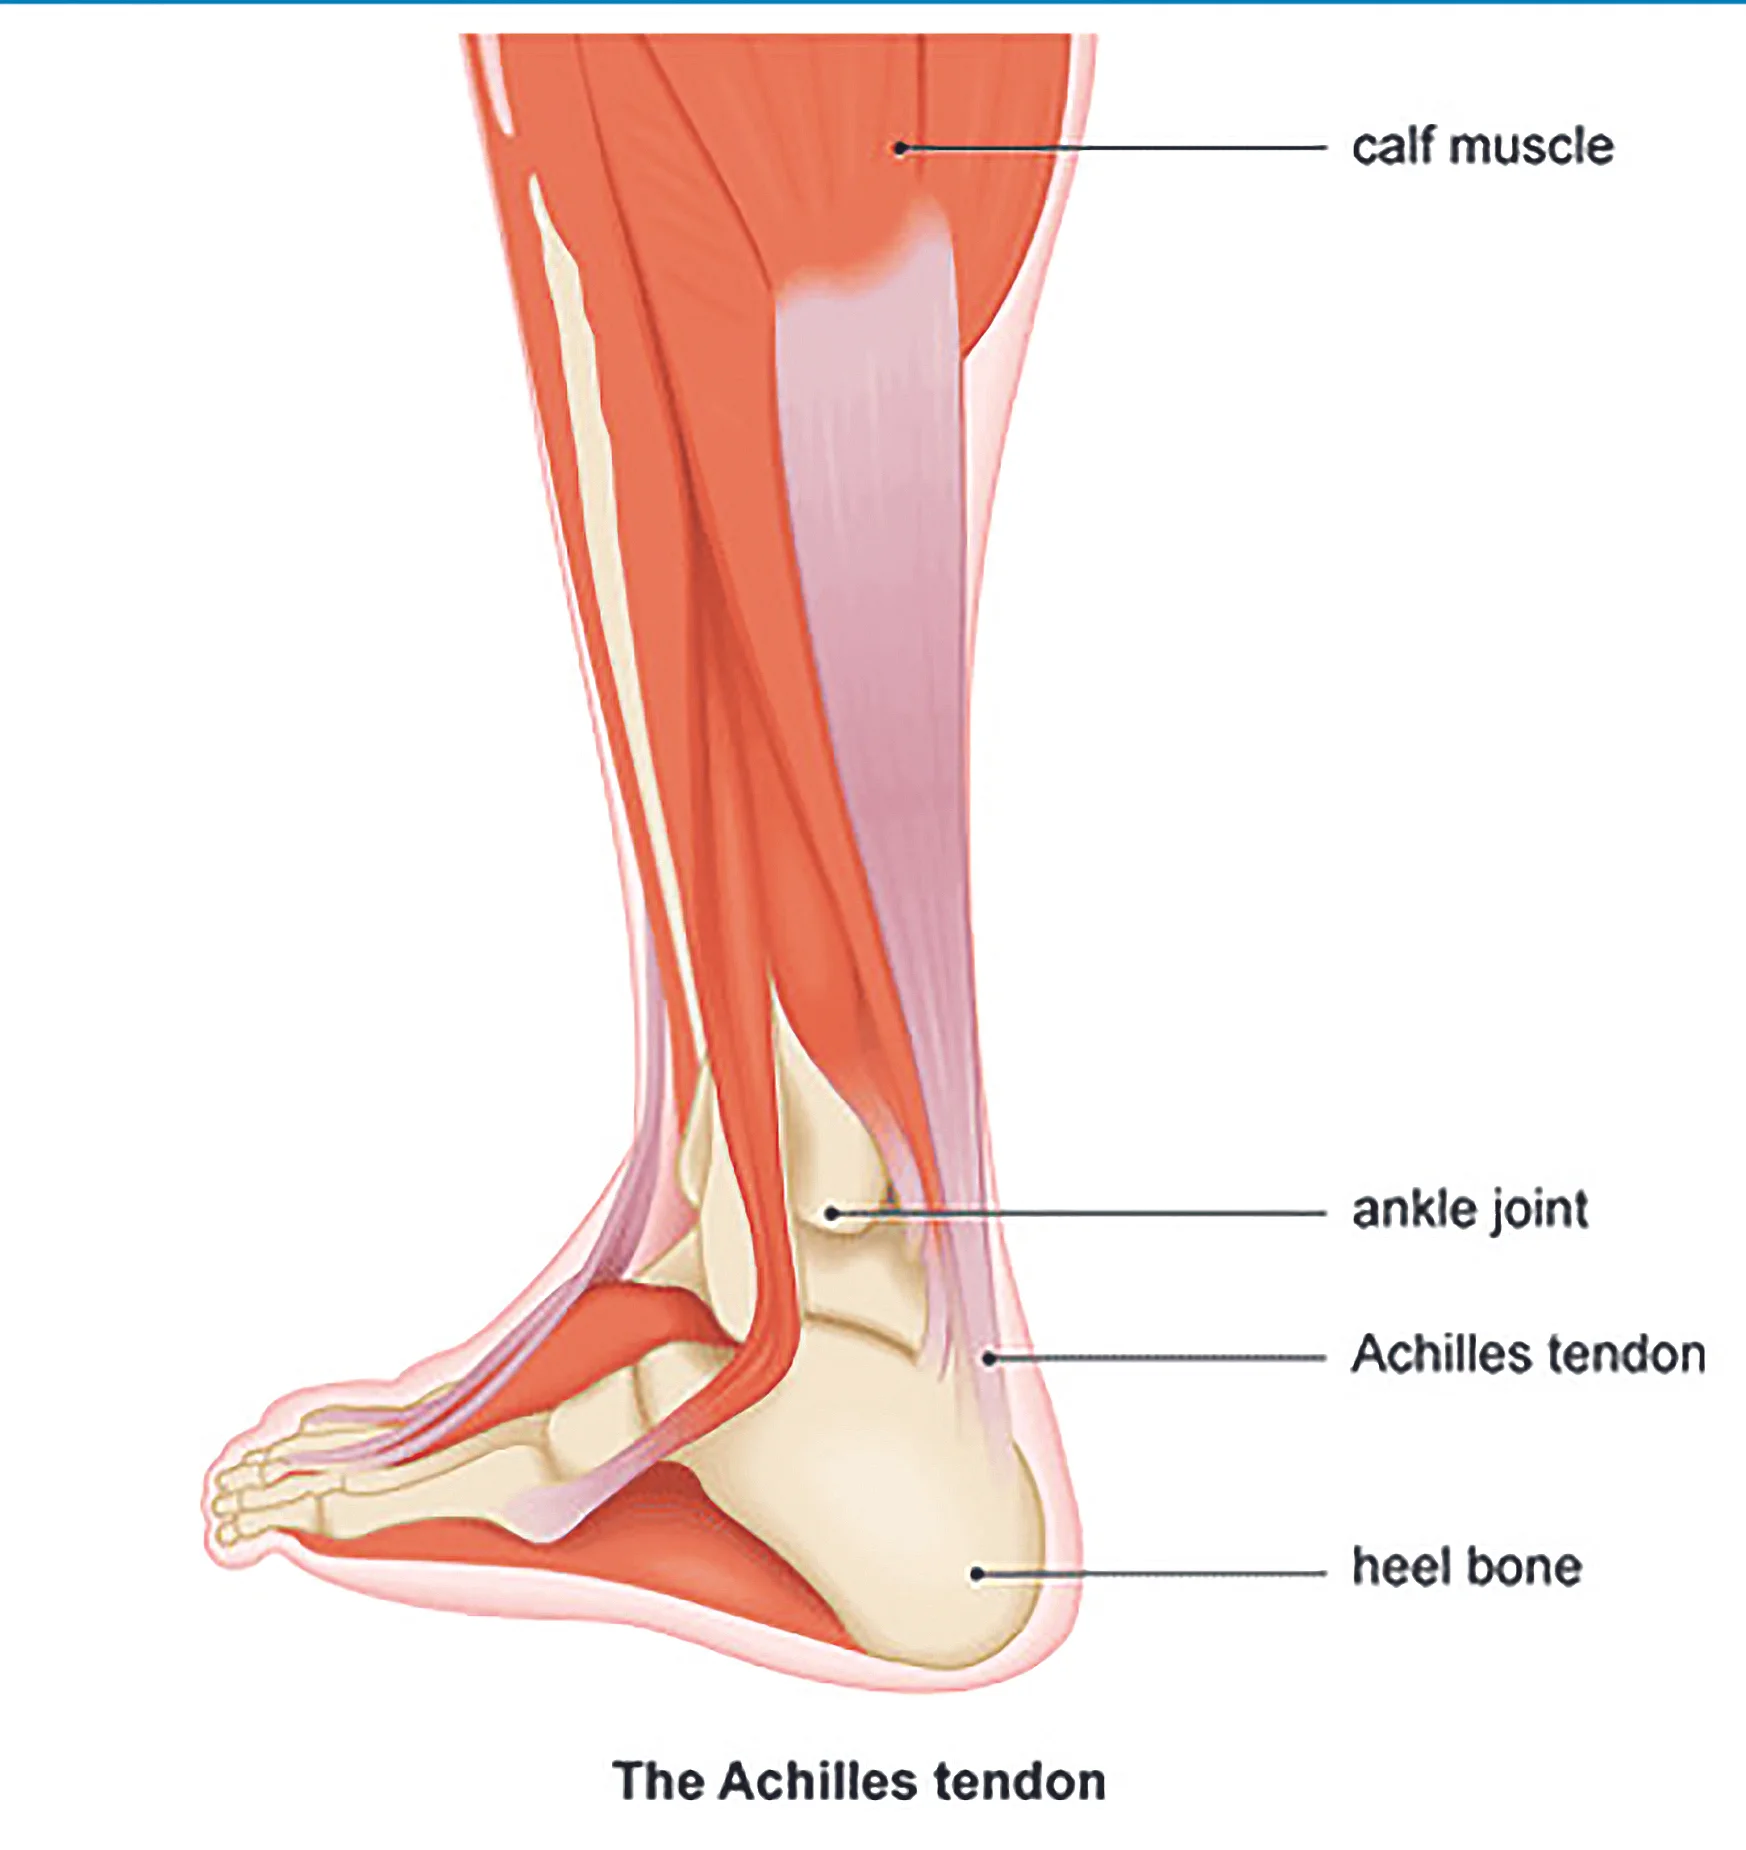

Achilles tendon injuries often cause pain, stiffness, and swelling in the back of your leg near your heel.

Apply ice over the achilles tendon for 15 to 20 minutes, 2 to 3 times per day. The achilles is the largest tendon in your body. Rest ice compression elevation 2 rest your leg.

Using ice and resting may help, but you also want to keep your tendon from moving around too much. It mainly occurs in people playing recreational sports, but it can happen to anyone. Achilles tendinitis treatment includes rest, physical therapy and supportive shoes.